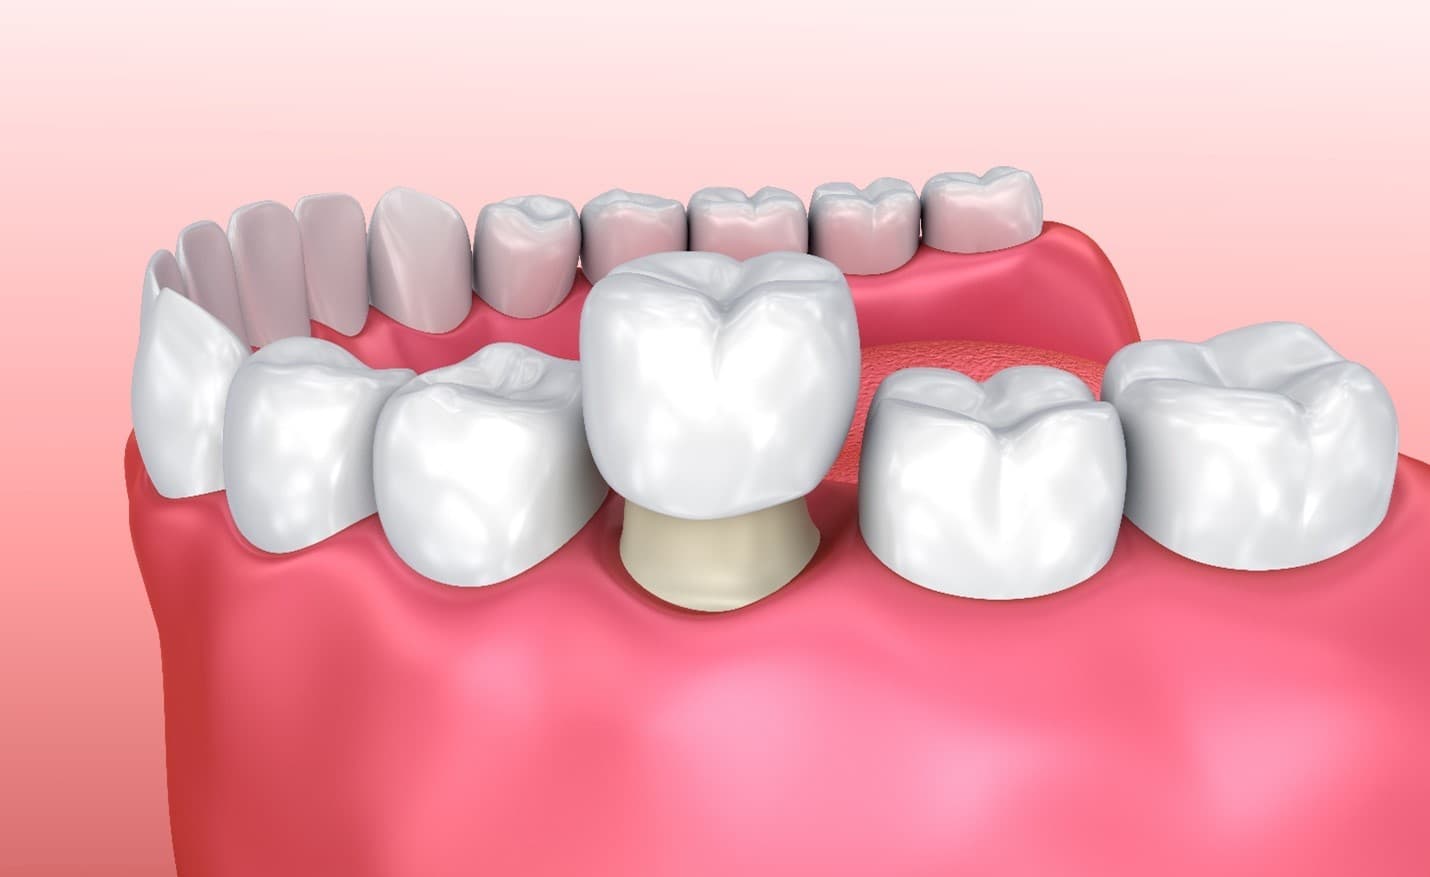

What Is a Dental Crown?

A dental crown is a custom-made ceramic cap placed over a damaged or weakened tooth to restore:

It fully covers the visible portion of the tooth, reinforcing its structure while improving aesthetics.